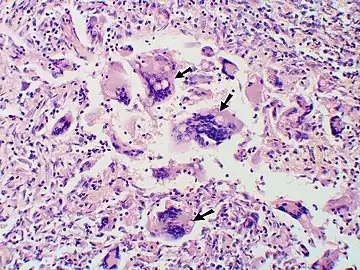

Granuloma with early suppuration. Fungal organisms difficult to recognize at this low magnification.

Large yeast-like fungi seen within giant cells at arrows.

Large yeast-like fungi seen within giant cells at arrows. Budding yeasts in cytoplasm of giant cells at arrows. Broad-based budding and double contoured cell wall seen in the giant cell in the center is characteristic of Blastomyces dermatitidis.